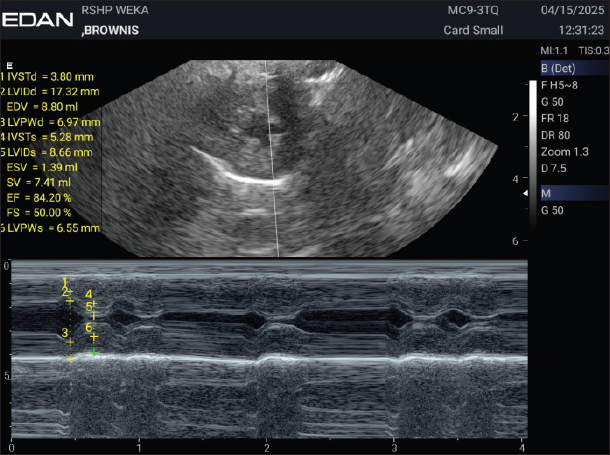

Figures 3 and 4 show the results of the echocardiographic examination, while Figure 5 presents the electrocardiographic findings of the dog, Brownis. The motion mode (M-mode) evaluation (Fig. 3) was used to measure the left ventricular dimensions during systole and diastole, as well as systolic and diastolic function values. The M-mode results showed a decrease in interventricular septal thickness during diastole and systole (IVSTd=5.28 mm, IVSTs=3.80 mm) and a reduction in left ventricular internal dimension during systole (LVIDs=8.66 mm). Figure 4 represents the brightness mode (B-mode) evaluation, used to assess valve thickening and movement. The results showed abnormal valve movement with normal valve structure. Figure 5 presents the electrocardiographic examination performed at a paper speed of 50 mm/second using a 5-lead system, which revealed sinus arrhythmia.

Fig. 3. M-mode Echocardiography of Brownis.

In the case of brownies, electrocardiography (ECG) showed an irregular rhythm with the presence of P waves, QRS complexes, a 1:1 P wave to QRS complex ratio, T waves, and a heart rate of 111 bpm. B-mode echocardiography revealed abnormal valve movement with normal valve structure. M-mode measurements were as follows: IVSTd 3.80 mm (normal 5.2–6.5 mm), LVIDd 17.32 mm (normal 15.83–18.53 mm), EDV 8.80 ml, LVPWd 6.97 mm (normal 5.1–6.1 mm), IVSTs 5.28 mm (normal 6.95–8.22 mm), LVIDs 8.66 mm (normal 9.01–11.5 mm), ESV 1.39 ml, SV 7.41 ml, EF 84.20% (normal 25%–55%), FS 50% (normal 55%–85%), and LVPWs 6.55 mm (normal 6.6–8.12 mm) (Cerbu et al., 2023). Color Doppler examination demonstrated turbulence at the valve, indicating abnormal blood flow velocity, visualized as red and blue gradients on the Doppler image. NT-proBNP levels were within normal limits at 0.5 ng/ml, whereas cardiac troponin I was elevated at 0.13 ng/ml, indicating myocardial cell injury.